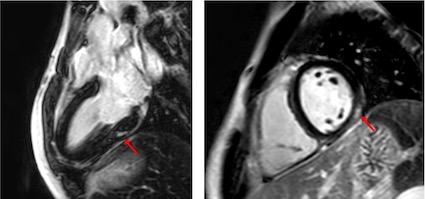

I pazienti avevano ricevuto una RM cardiaca di follow-up con un intervallo mediano di 3 mesi, fino ad un massimo di 9 mesi. Una disfunzione lieve del ventricolo sinistro era presente nel 20% dei pazienti, tutti però con ecocardiografia alla dimissione nella norma. Meno frequenti i segni di edema miocardico (5%) e il riscontro di una falda di versamento pericardico (5%), in accordo con la letteratura esistente1. Un pattern di enhancement tardivo del gadolinio, espressione di fibrosi cicatriziale, caratterizzava il 25% dei pazienti, benché minimo per entità (Figura 1). Le cicatrici miocardiche sono esiti tipici delle miocarditi, sia virali che immuno-mediate2. Sebbene non sia possibile predire l’evoluzione di tali cicatrici in pazienti affetti da MIS-C, in uno dei pazienti inclusi in questo studio, rivalutato con RM cardiaca dopo 7 mesi, si era osservata una riduzione dell’entità dell’esito cicatriziale.